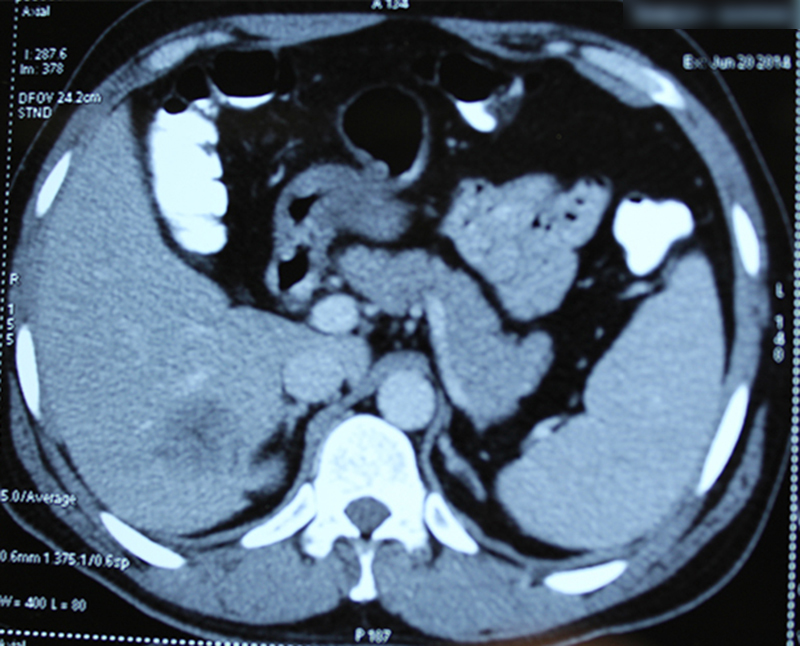

45 year old gentleman was diagnosed with right colon cancer (poorly differentiated adenocarcinoma) and solitary metastasis to liver. He underwent a one stage surgery (right hemicolectomy for colon cancer and resection of liver metastasis). The surgery was followed by multiple cycles of chemotherapy. A chemoport was placed for the same. The patient lived for 4 years after diagnosis of advanced poorly differentiated colon cancer.

Patients diagnosed or suspected to have a colon / rectal cancer are subjected to multiple tests. The most important ones are checking serum tumor marker CEA (carcinoembryonic antigen), colonoscopy and biopsy, CT scan of abdomen & pelvis and sometimes a PET CT study. The CEA is useful in diagnosing cancer and also to follow treatment response (surgery or chemotherapy). However all patients may not have a raised CEA. CT / PET-CT is done to see if tumor can be operated and removed or has it spread beyond the intestine in the surrounding area or distant organs like liver, lungs etcetera. A colonoscopy ( endoscopy of large intestine to visualize it from within) helps to take a biopsy and also checks whether cancer is in only one part or multiple parts of colon (synchronous primary tumor). The biopsy sample is run through many tests apart from regular histopathology. This includes immunohistochemistry (IHC), genetic tests for mutations (KRAS, BRAF, microsatellite instability) etcetera. These tests help in deciding prognosis, treatment plan treatment sequence, chemotherapeutic drugs to be used. In short have a major impact on treatment. However they are very expensive too.